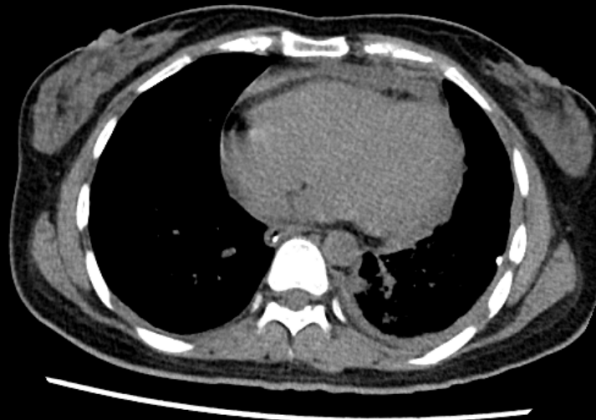

2021-03-13 我院心脏超声示心包积液。胸部超声示双侧胸腔积液。腹部超声示腹腔未见明显积液。胸部平扫(CT)提示前纵隔占位性病变,左侧心膈角区淋巴结;左侧大量胸腔积液,右侧少量胸腔积液,左肺局部膨胀不全,右肺中叶小结节,纵隔略右偏,心包大量积液。

3.多浆膜腔积液 患者心超示大量心包积液,且存在呼吸急促及胸闷情况,评估血流动力学状态,请相关科室会诊,必要时行心包穿刺;患者多浆膜腔积液,送检结核、肿瘤、病毒等相关病原学检查。

患者有胸闷气促及氧合差的情况,予行心包穿刺及胸腔穿刺,同时送检了心包积液及胸腔积液的相关检查。

患者经过穿刺引流后氧合明显改善,鼻导管吸氧下呼吸氧合可,血流动力学基本稳定,转普通病房治疗。同时复查了肺部CT。

患者存在纵隔肿块,经过同意后予超声引导下行肿块穿刺活检。病理结果提示:恶性淋巴瘤。后期血液肿瘤科进行了专科治疗。